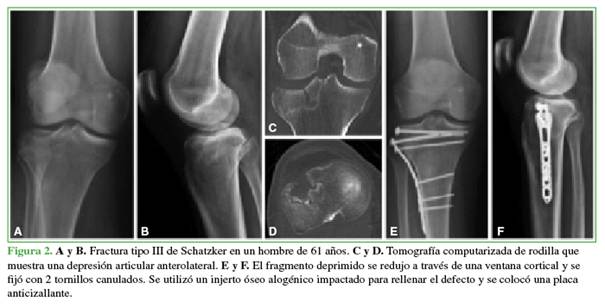

Tras la reducción, se procedió a la fijación preliminar con agujas de Kirschner. En el grupo con técnica derafting (Figura 1), la fijación definitiva se hizo con tornillos subcondrales de 3,5 mm a través de la placa cuando su diseño permitía una colocación adecuada de los tornillos subcondrales. En caso contrario, los tornillos se colocaron proximalmente fuera de la placa.

En el otro procedimiento, se restituyó la superficie articular con aloinjerto óseo impactado desde una ventana distal, se colocaron 2 tornillos canulados (de 4,5 o 6,5 mm) y luego se impactó y rellenó nuevamente con aloinjerto para ocupar el defecto metafisario (Figura 2).

En las fracturas tipo II, se colocó una placa bloqueada de bajo perfil como contrafuerte, mientras que, en las fracturas tipo III, su uso quedó a discreción del cirujano encargado.